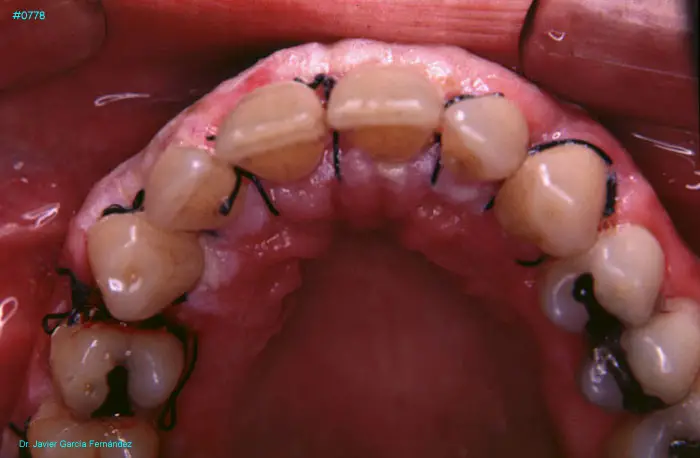

Atlas of Surgical Techniques in Periodontics. Chapter III. Atlas de Técnicas Quirúrgicas en Periodoncia

image156